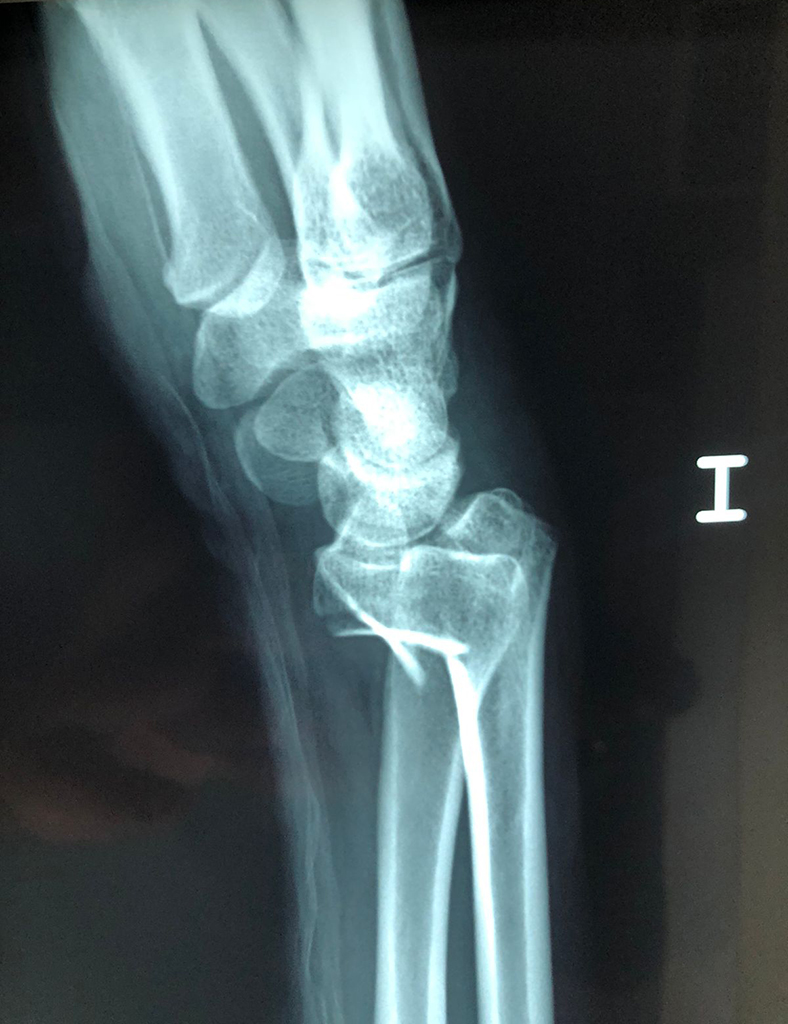

Cirugías de Húmero - Cirugías de Muñecas y Manos

Los procedimientos más comunes en cirugía de la mano son aquellos destinados a reparar traumatismos, incluyendo lesiones de tendones, nervios, vasos sanguíneos, y articulaciones; huesos fracturados; y quemaduras, cortes, y otros daños de la piel.